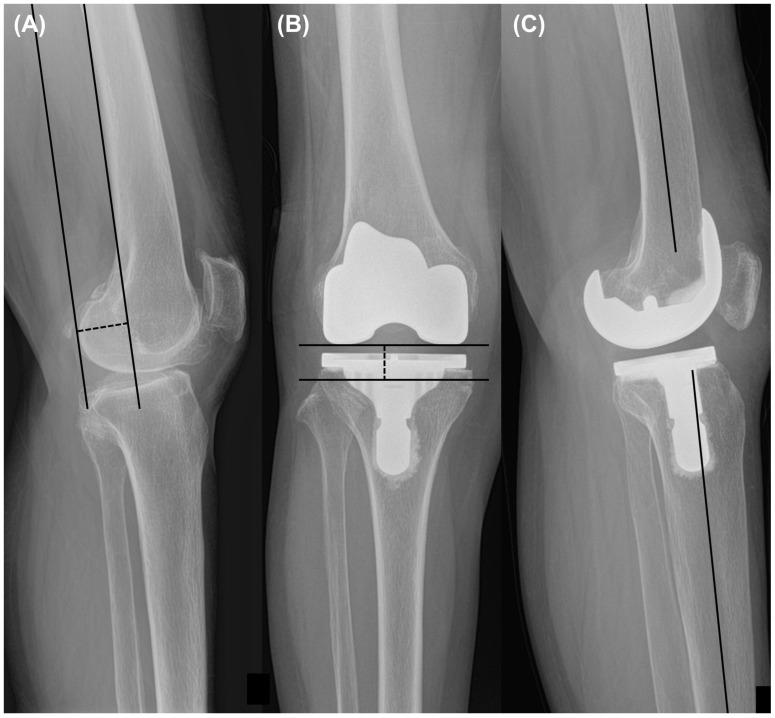

The purpose was to compare the clinical and radiographic outcomes between preoperative mild and severe varus deformity after total knee arthroplasty (TKA) with medial stabilizing technique (MST). We retrospectively analyzed 158 knees of 125 female patients with a 2-year follow-up who underwent mechanically aligned TKA with MST between April 2018 and February 2021. Patients were divided into two groups; the severe varus group was defined as one with preoperative hip-knee ankle (HKA) angle ≥ 15° and the mild varus group with HKA angle < 15°. Pre- and post-operative clinical outcomes (Western Ontario and McMaster University Osteoarthritis Index, Knee Society Knee Score) and radiographic outcomes (medial proximal tibial angle (MPTA), HKA angle, lateral distal femoral angle (LDFA), joint line distance, and femoral component rotation angle) were compared between the groups. Among the 158 knees analyzed, 131 and 27 were allocated to the mild and severe varus groups, respectively. Preoperative data showed that the MPTA (84.7° ± 2.8° vs. 80.7° ± 3.2°, < 0.001) was significantly less in the severe varus group. In postoperative data, clinical outcomes were not different between the groups. Joint line distance (18.4 mm ± 2.8 mm vs. 18.6 mm ± 2.7 mm, = 0.676) was also not significantly different. Femoral component rotation angle (-1.7° ± 1.0° vs. -1.0° ± 1.3°, = 0.018) was more externally rotated in the severe varus group. Severe varus group showed comparable clinical and radiographic outcomes to that of mild varus group after mechanically aligned TKA with MST.

目的是比较采用内侧稳定技术(MST)的全膝关节置换术(TKA)后术前轻度和重度内翻畸形之间的临床和影像学结果。我们回顾性分析了2018年4月至2021年2月期间接受MST机械对线TKA的125例女性患者的158个膝关节,随访2年。患者分为两组;重度内翻组定义为术前髋-膝-踝(HKA)角≥15°,轻度内翻组HKA角<15°。比较两组术前和术后的临床结果(西安大略和麦克马斯特大学骨关节炎指数、膝关节协会膝关节评分)和影像学结果(胫骨近端内侧角(MPTA)、HKA角、股骨远端外侧角(LDFA)、关节线距离和股骨假体旋转角)。在分析的158个膝关节中,分别有131个和27个被分配到轻度和重度内翻组。术前数据显示,重度内翻组的MPTA(84.7°±2.8°对80.7°±3.2°,<0.001)明显更小。术后数据显示,两组临床结果无差异。关节线距离(18.4 mm±2.8 mm对18.6 mm±2.7 mm,=0.676)也无显著差异。重度内翻组的股骨假体旋转角(-1.7°±1.0°对-1.0°±1.3°,=0.018)更向外旋转。在采用MST进行机械对线TKA后,重度内翻组的临床和影像学结果与轻度内翻组相当。